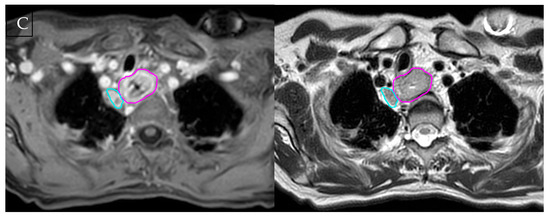

Figure 1.

Multimodality imaging comparison in oesophageal cancer. (A) Axial contrast-enhanced CT at the thoracic inlet. (B) 18F-FDG PET/CT at the same level shows avid uptake consistent with a metabolically active tumour, but with limited spatial resolution, especially in the adjacent node. (C) T1 and T2-weighted MRI with gross tumour volume (pink) and suspicious node (blue) contoured. Although the tumour abuts the trachea, MRI clearly demonstrates an intact interface and preserved tracheal cartilage. All images were acquired on the authors’ institutional MR-Linac and are presented for illustration only.